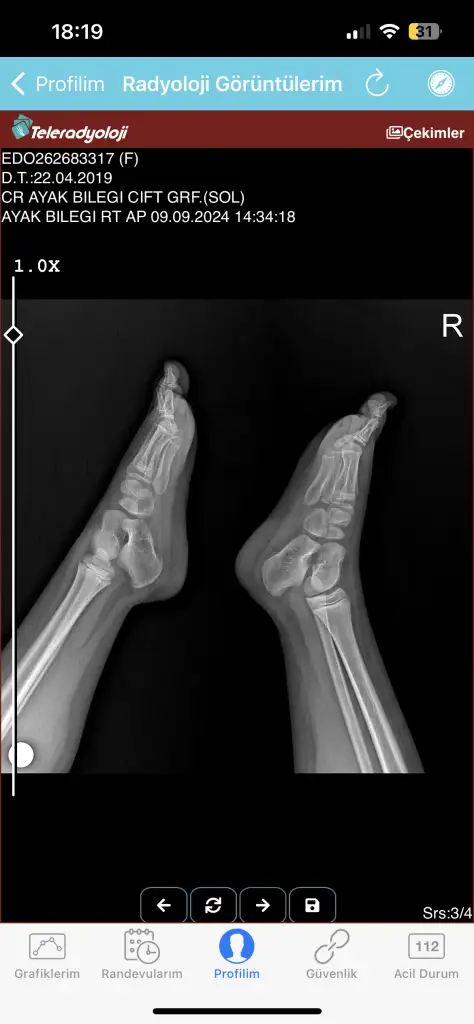

Merhaba benim kızım 4 gün önce bisikletten düştü ve ayağı yaralandı şişti doktora götürdüm doktor röntgen çekti röntgende pek bir şey görünmedi pansuman yapıp yolladılar iki gün sonra yani bugün pansumanını açtım ayağı daha kötü olmuş ve şişmişti kesinlikle üstüne basamıyor ve dokun durmuyor bugün yine gittim röntgen ve tomografi çekti tomografi raporunu ve röntgeni ekliyorum acaba anlayan bilen var mı bilen varsa yazabilir mi rica etsem ayağı çok kötü durumda çünkü korkuyorum bir şey olur diye

Kirik yok, catlak da yok, yumuşak doku zedelenmesi var. O da oldukca agri yapar cok yasamisligim var.

Agri kesici kullanmasi gerekebilir.